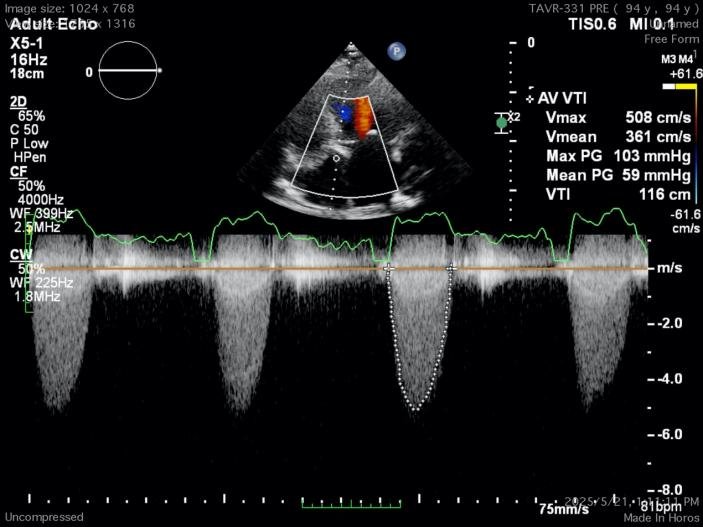

心脏超声示:

起搏器安置术后,主动脉瓣病变,退行性变可能性大,主动脉瓣狭窄(重度),左心大,左室心肌轻度肥厚,二尖瓣退行性变伴轻度反流,肺动脉压力轻度升高,三尖瓣反流(轻度)。

主动脉瓣左、右、无冠瓣弥漫性增厚,钙化,回声增强,开放受限,跨瓣血流速度加快,峰值压差约80mmHg,平均压差约44mmHg,关闭时探及微量反流。EF:56%,左室52mm。

术前心脏超声上可以看到阿婆使用了94年的瓣膜增厚、僵硬、钙化,这颗94岁的心脏平均承受着59mmHg的压力来维持叶奶奶的生命,心脏的血液以5m/s以上的速度射出狭窄的主动脉瓣口来给全身供血,主动脉瓣重度狭窄的诊断明确。